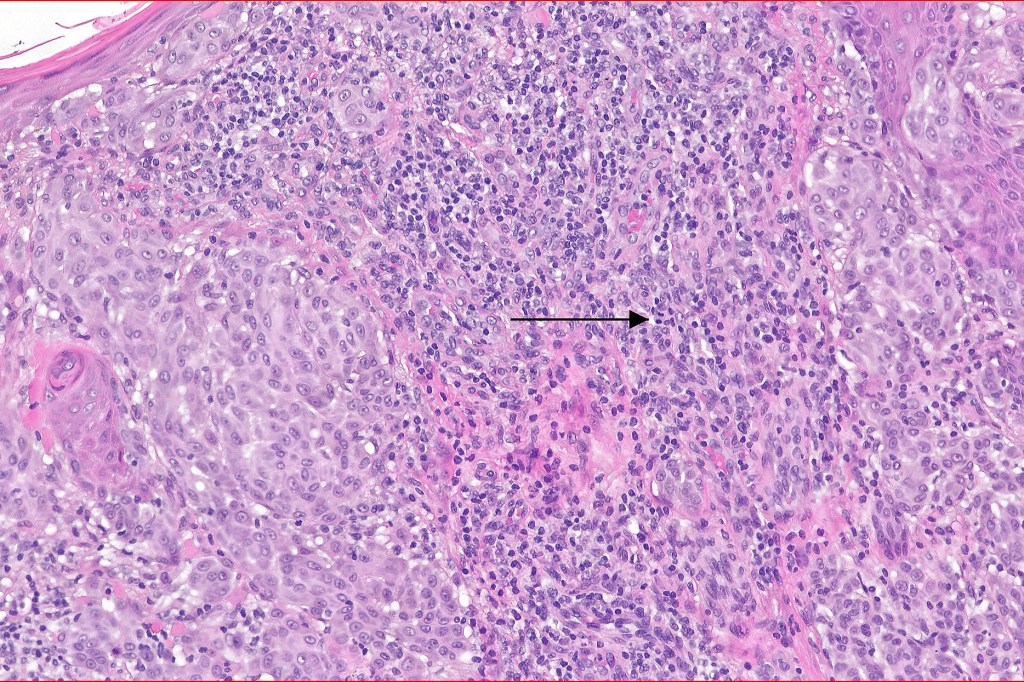

Histological features

•>5-10 mm

•Involve deep dermis or subcutis

•Asymmetrical, poorly circumscribed

•May show effacement/consumption of epidermis or ulceration

•Peripheral Pagetoid spread

•Large nodules which often show impaired maturation

•Loss of gradient with HMB45 and Ki67

•>20% Ki67 expression

•TERT promoter & PTEN mutations

•DNA copy-number variations